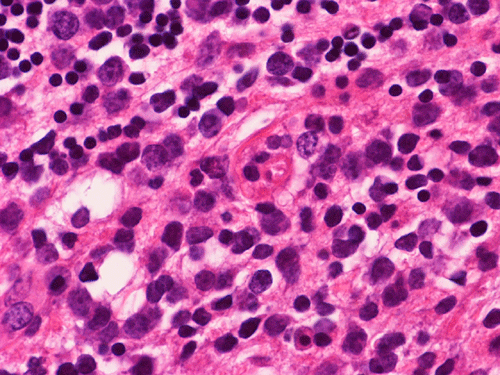

The biopsy material is obtained from the cerebellum. It is composed of two small fragments of semi-liquid dark, mucoid tissue, 0.4 x 0.4 x 0.2 cm in toto. Half is used for the cytologic preparation and the other half for frozen section. On scanning and low magnifications of the intraoperative cytologic preparation (Panel A and B) there are numerous rather monotonous cells. On high magnification (Panel C), these cells have monotonous, large, hyperchromatic and round nuclei with a prominent nucleoli in many of them. There is an extremely high nuclear to cytoplasmic ratio and these cells have only a thin rim of cytoplasm around them. Some naked nuclei are also present. The cells do  not really cluster together. Frozen section shows small fragments of cerebellar tissue infiltrated by these abnormal cells  (Panel D and E). In these areas, residual molecular layer and internal granular cells are present. The tumor cells has a diffusely infiltrative pattern. On high magnification (Panel F), the atypical cells have nuclei far larger than those of the internal granular cells (arrow in Panel F).

The leading differential diagnosis in this case is lymphoma.  Metastatic malignant melanoma can also give  a plasmacytoid pattern on cytologic preparation and should be considered in this case.  However, metastatic melanoma with plasmacytoid pattern usually has more prominent nucleoli, pseudonuclear inclusions, more prominent nucleoli and variation in tumor size and they also have a higher tendency to form small clusters.  Obviously if melanin pigment can be demonstrated than the diagnosis of metastatic melanoma could be confirmed but this is not a particularly common scenario. Poorly differentiated metastatic carcinoma particularly small cell carcinoma should also be considered.  However, it is quite uncommon to see absolutely no clustering in a case of metastatic carcinoma. In addition, metastatic small cell carcinomas typically have "salt and pepper" nuclei, typical for neuroendocrine tumors. The cytologic preparations really does not suggest high grade glioma but glioblastomas should not be forgotten.